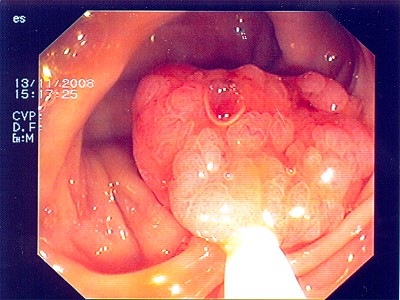

Gut sichtbarer Blutstrahl nach Abtragung eines Polypen